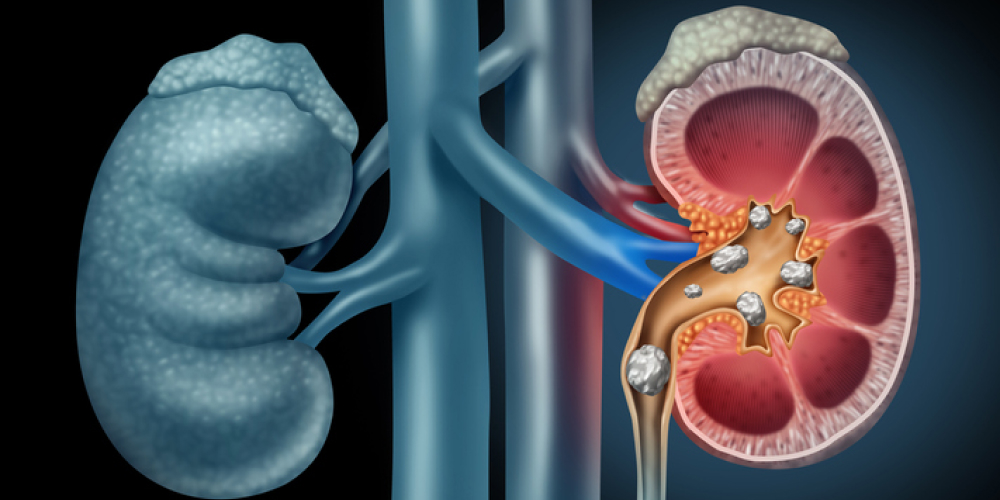

Everything You Need to Know About Kidney Stones

Kidney or renal stones are irregularly shaped masses of minerals and hard deposits formed inside the kidneys. They can be as small as a grain of rice or as large as a golf ball. According to the top nephrologist in Jaipur,

Knowing about Kidney Tests and Procedures

Kidney health is the foundation stone of overall physical well-being. Most importantly, it helps in waste elimination from the body and keeps all the water and nutrient levels in the body balanced. If you are facing kidney-related issues, then it

Early Warning Signs of Kidney

Understand Kidney Disease in Women Kidney disease arises when your kidneys sustain damage and are unable to effectively filter blood. This results in an accumulation of waste and fluid within the body. It may be acute (happening suddenly) or chronic (progressing gradually over time). Acute kidney disease can get better with treatment, whereas chronic kidney disease typically needs ongoing management. In addition to filtering the blood, kidneys assist in regulating blood pressure, generating red blood...